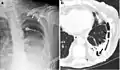

A fibrothorax can typically be diagnosed by taking an appropriate medical history in combination with the use of appropriate imaging techniques such as a plain chest X-ray or CT scan.[3] These imaging techniques can detect fibrothorax and pleural thickening that surround the lungs.[7] The presence of a thickened peel with or without calcification are common features of fibrothorax when imaged.[3] CT scans can more readily differentiate whether pleural thickening is due to extra fat deposition or true pleural thickening than X-rays.[3]

If a fibrothorax is severe, the thickening may restrict the lung on the affected side causing a loss of lung volume.[7] Additionally, the mediastinum may be physically shifted toward the affected side.[3] A reduction in the size of one side of the chest (hemithorax) on an X-ray or CT scan of the chest suggests chronic scarring.[6] Signs of the underlying disease causing the fibrothorax are also occasionally seen on the X-ray.[6] A CT scan may show features similar to those seen on a plain X-ray.[7] Lung function testing typically demonstrates findings consistent with restrictive lung disease.[6]

Extensive left-sided fibrothorax

Chest radiograph displaying inhomogeneous opacification of the left half of the chest that is fibrothorax